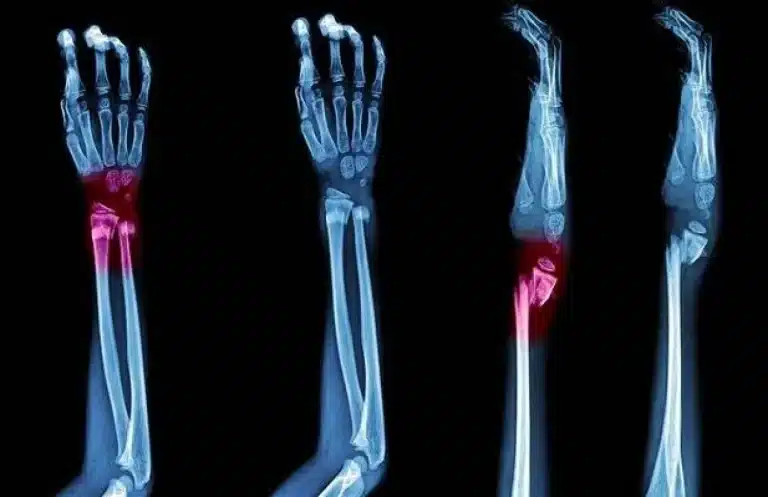

أعشاب تساعد على التئام عظام الساعد

الساعدة يعتبر من أكثر المناطق العظمية التعرض لكسر حيث تتكون من عظمتين أساسيتين وهما الكعبرة والزند وهما عظمتان…

تتعدد كسور الذراع وتختلف حسب الإصابات التي يتعرض لها الأفراد، ولكل منها طريقة علاج مختلفة يتوقف على شدة…